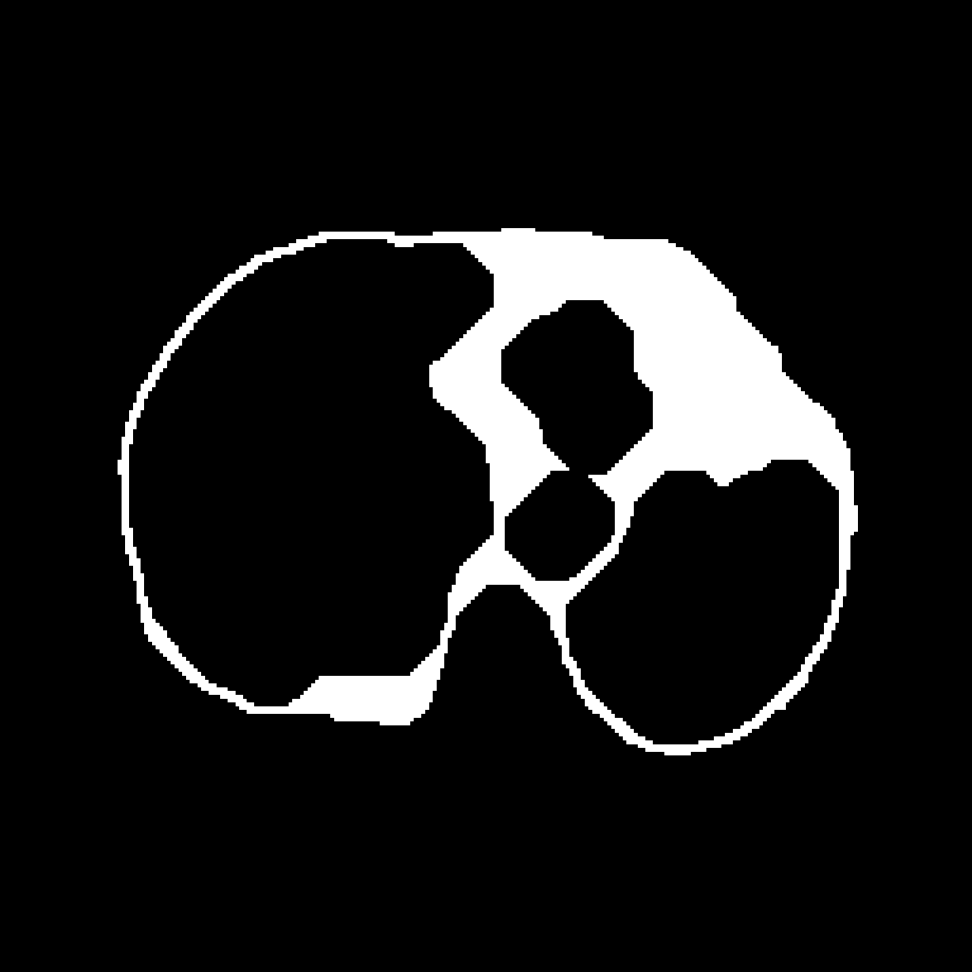

For the binary disease classification/survival prediction tasks, we used a conservative approach, thresholding the voxels at -570 HU and using morphological closing and opening operations to create smooth lung masks that contain lung parenchyma and air. To further include pathological signs such as fungus balls and pleura-thickening, we refined the approach from [4] and [5]. First, we define a set of markers. To do so, pixels are thresholded at -570 HU and connected components are extracted, while removing the smallest ones. These connected components provide internal markers. Then, we define intermediate and external markers, via morphological dilation of internal markers with structuring elements of radius 10 and 35 pixels, respectively. These markers define the spatial extent of the region where lung tissues can be added to the threshold-based segmentation. To find the lung structures to add, a watershed segmentation (Fig. 2(b)) is used, with seeds generated with a Sobel-filter edge map. It returns large homogeneous connected regions but still excludes some diseased structure with soft-tissue like attenuation values. A top-hat transform (Fig. 2(c)) is used, where the occluded region is initially morphologically closed and then the difference between the original and the closed structure is added to the watershed mask. The final segmentation mask (Fig. 2(d)) is generated after closing the remaining holes.

Refer to caption

(a) Axial slice

(b) Watershed

(c) Outline

(d) Closing

Fig. 2: Illustrations of the segmentation of the lung area